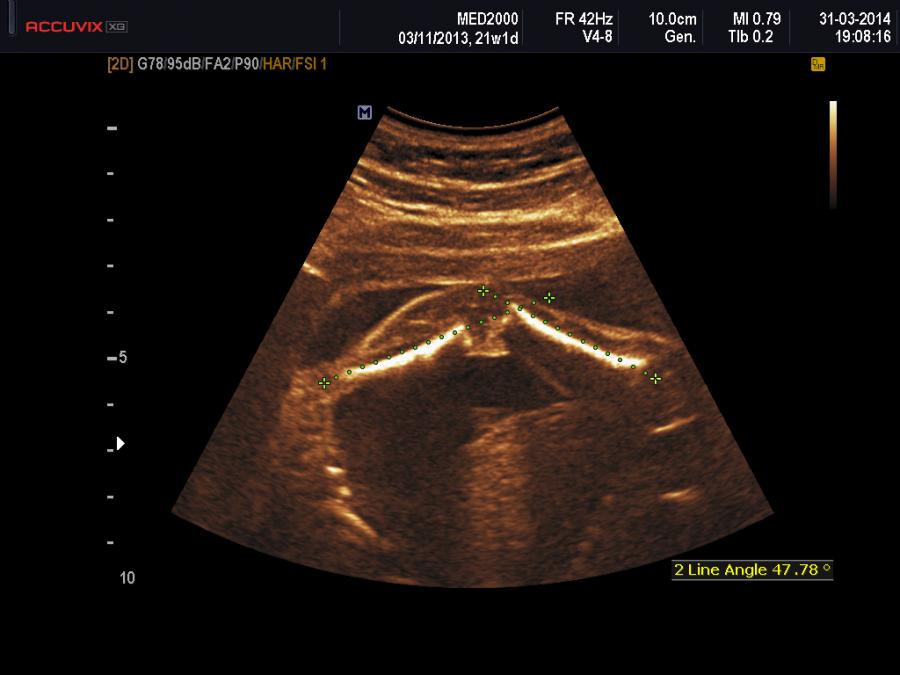

La diagnosi prenatale può essere sospettata se presenti alcune anomalie muscolo-scheletriche: ginocchio recurvato congenito, micrognazia, dislocazione del radio, piede torto, spondilolisi, spondilolistesi.